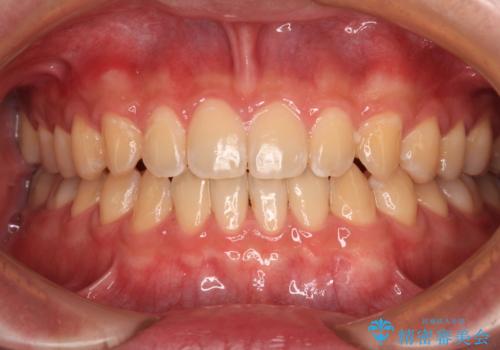

舌の突出癖がなかなか改善されず、治療期間は当初予定よりも大分長くなりました。

装置除去を予定していた日に、油断されたのか1mmほどのスペースを作ってしまったため、除去が3ヶ月延長されたことで、舌のトレーニングの重要性を理解していただきました。

装置除去後もトレーニングを継続されているようで、後戻りによるスペースは今のところ認められておりません。